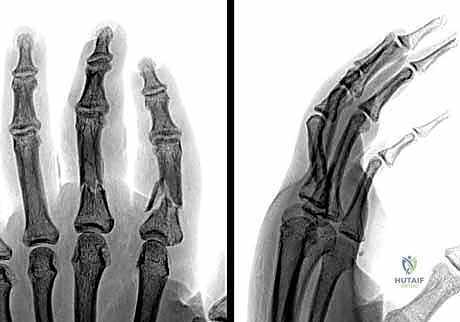

- التصوير بالأشعة السينية (X-rays): هو المعيار الذهبي لتشخيص كسور السلاميات. يطلب الدكتور هطيف دائماً ثلاث وضعيات أساسية:

- الأمامية الخلفية (AP View).

- الجانبية الحقيقية (True Lateral View): وهي الأهم لتقييم مقدار الانزياح الزاوي.

- المائلة (Oblique View): تساعد في رؤية الكسور الشعرية الدقيقة أو الكسور المفصلية الخفية.

- التصوير المقطعي المحوسب (CT Scan): في حالات الكسور المفتتة جداً أو المعقدة، قد يُطلب إجراء فحص مقطعي للحصول على صورة ثلاثية الأبعاد تساعد في التخطيط الجراحي الدقيق.

1. الرد المغلق والتثبيت بأسلاك كيرشنر (CRPP - Closed Reduction and Percutaneous Pinning):

تُعد هذه الطريقة الأقل توغلاً. يقوم الدكتور هطيف برد الكسر يدوياً تحت توجيه جهاز الأشعة السينية المباشر (C-arm) في غرفة العمليات، ثم يقوم بإدخال أسلاك معدنية دقيقة (K-wires) عبر الجلد لتثبيت العظم.